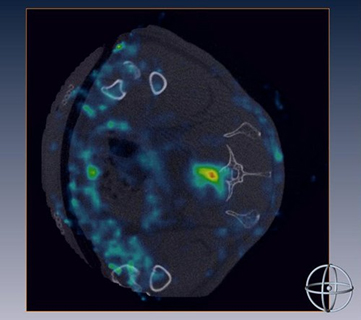

| Human stem cells, isolated from bone marrow, home to a fractured and osteoporotic vertebra. |

This research has shown that in animals with osteoporosis and vertebral fractures treated with intravenous injections of MSCs and PTH, we could detect enhanced MSC homing to the fracture sites, leading to rapid bone repair.